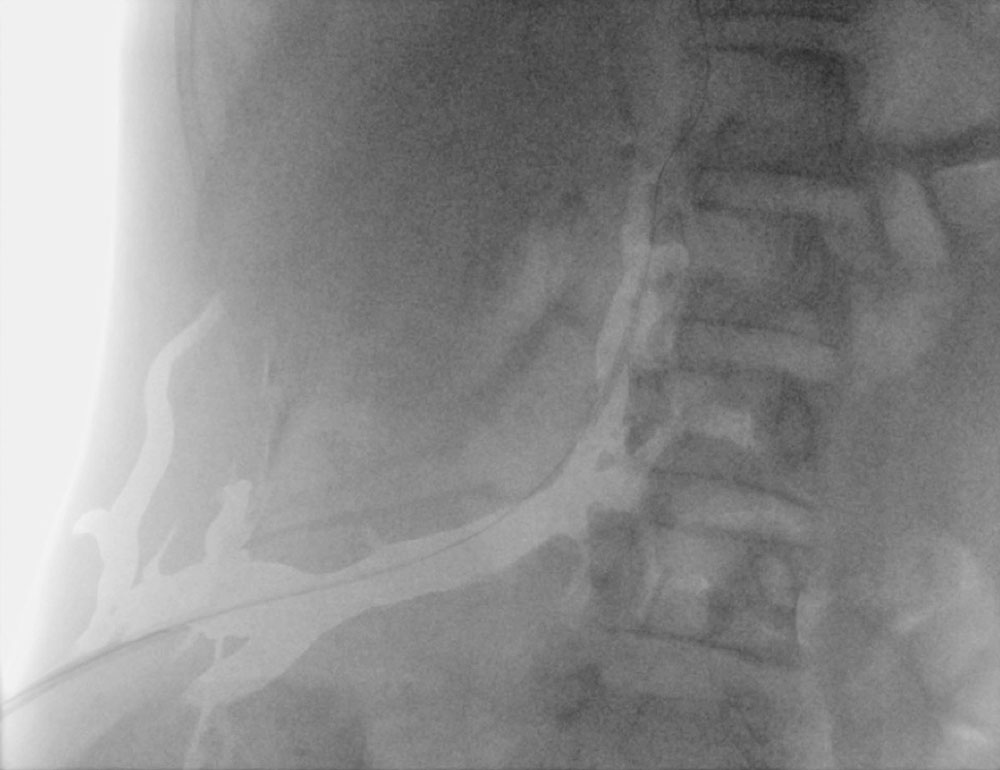

Vascular malformations can involve capillaries (CM), veins (VM), and/or lymphatic vessels (LM); furthermore, arteriovenous malformations (AVM) may occur more rarely. Capillary malformations (initially often purplish, later fading) in the trunk area are characteristic. Venous malformation often results in large marginal veins that may extend into the thorax. The arteriovenous malformations are often located near or interspersed in the lipomatous masses; they are also clustered paraspinally.